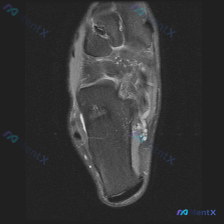

这是一张足部冠状位液体敏感序列(T2-FS/STIR)MRI,图像对比度良好,无明显伪影,主要显示后足跟骨、距骨及踝关节周边软组织。

- 骨骼:跟骨信号均匀,未见皮质中断、骨质破坏,属于正常表现

- 病变:踝关节内侧及跟骨内侧软组织间隙内,可见多发、串珠状/簇状分布的囊状高信号病灶,边界清晰,符合液体/积液信号特征

- 其他:周边肌腱信号正常,病灶无明显占位效应,也没有观察到骨侵蚀征象